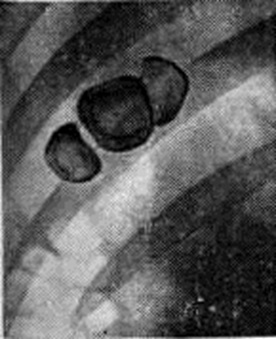

Окончательный диагноз хронический холецистита устанавливают после проведения рентгенологическое и инструментального обследований. Важным методом исследования при хронический холецистите является рентгенологический. Начинать обследование следует с обзорной рентгенографии (смотри полный свод знаний) области правого подреберья, при которой можно обнаружить тени рентгеноконтрастных камней (рисунок 2) или обызвествление стенок желчного пузыря (рисунок 3). После этого производят холецистографию (смотри полный свод знаний) или сочетанную холецистохолангиографию, позволяющие установить наличие в желчном пузыре камней, что проявляется дефектом наполнения (рисунок 4), а также выявить деформацию желчного пузыря (рисунок 5) и нарушение его функции при некалькулёзном холецистите. С помощью ультразвукового исследования определяют состояние стенки пузыря, наличие в нем конкрементов, а также сократительную способность желчного пузыря. Все большее распространение получают метод радиоизотопного исследования желчного пузыря (смотри цветной рисунок 12 и 13), а также компьютерная томография печени, желчного пузыря (рисунок 6) и поджелудочной железы, которые применяются прежде всего у больных с желтухой и у лиц, которым противопоказано (например, в связи с аллергией) обычное рентгенологическое исследование. У больных с желтухой и (или) при непереносимости контрастного вещества (при его внутривенном введении) для уточнения диагноза можно произвести ретроградную холангиографию (смотри полный свод знаний) во время фибродуоденоскопии. Это даёт возможность получить прямое контрастирование желчного пузыря, позволяющее при некалькулёзном холецистите выявить его деформацию (рисунок 7) и нарушение оттока желчи, при калькулёзном холецистите — конкременты в просвете желчного пузыря, а иногда в общем желчном протоке. Дифференциальный диагноз. Хронический холецистит следует дифференцировать с язвенной болезнью, хронический воспалительными заболеваниями мочевыводящих путей и толстой кишки. Дифференциальную диагностику между хронический холециститом и язвенной болезнью проводят на основании особенностей болевого синдрома, сезонности обострений, данных рентгенологического и эндоскопического исследований (смотри полный свод знаний: Язвенная болезнь). При хронический заболеваниях мочевыводящих путей боли иррадиируют в паховую область, отмечаются дизурические явления, изменения в моче. Хронический воспалительные заболевания кишечника исключаются на основании данных рентгенологического и эндоскопического исследования (смотри полный свод знаний: Колит). Лечение. Хронический калькулёзный холецистит и осложнённые формы хронический некалькулёзного холецистита подлежат оперативному лечению (смотри полный свод знаний: Желчнокаменная болезнь, Холецистэктомия). Консервативно лечат неосложнённые формы некалькулёзного холецистита и обострения других форм хронический холецистита, когда больной категорически отказывается от оперативного лечения или проведение его невозможно из-за тяжёлых сопутствующих заболеваний. Консервативные мероприятия направлены на ликвидацию воспалительного процесса, борьбу с застоем желчи и дискинезией желчных путей. Больным назначают постельный или полупостельный режим, дробное питание, щадящую диету (смотри полный свод знаний: выше Острый холецистит), которую расширяют при улучшении самочувствия через 2 недель, противовоспалительные средства (антибиотики или сульфаниламиды) в течение 2—3 недель Применение желчегонных средств зависит от типа сопутствующей дискинезии. При дискинезии по гипотоническому типу показаны холецистокинетики — сульфат магния, карловарская соль, оливковое масло, гипофизин, сорбит, ксилит и другие При дискинезии по гипертоническому типу целесообразно применять холеретики (холагол, холосас), а а также спазмолитические средства (атропин, препараты белладонны, ношпа, платифиллин и другие). При затруднении в определении типа дискинезии, а также в случаях смешанных дискинезий рекомендуют желчегонные средства растительного происхождения (отвар кукурузных рылец, шиповника и другие), обладающие сочетанным (в большей степени холеретическим) умеренным эффектом. При сочетании холецистита с дискинезией по гипертоническому типу рекомендуют также седативные средства (препараты валерианы, пустырника, бром и другие). В случае вовлечения в патологический процесс поджелудочной железы в комплекс лечебный мероприятий включают ферментную терапию (смотри полный свод знаний: Панкреатит). При хронический некалькулёзном холецистите с упорным течением и наличием у больного аллергических реакций рекомендуются антигистаминные средства (димедрол, супрастин и другие), в случае иммунной недостаточности — левамизол. Эффективным при хронический холецистите является дуоденальное зондирование или беззондовый тюбаж (смотри полный свод знаний), а также водолечение. При дискинезии по гипотоническому типу назначают щелочные воды с высокой минерализацией (Ессентуки № 17, Арзни, Баталинская), при дискинезии по гипертоническому типу — подогретую минеральную воду с меньшей концентрацией солей и более низким содержанием газа (Ессентуки № 4, № 20, Славяновская, Смирновская, Железноводская). При назначении минеральной воды следует учитывать состояние секреторной функции желудка. Физиотерапевтические процедуры показаны при хронический холецистите вне обострения. Наиболее эффективны: диатермия (смотри полный свод знаний), индуктотермия (смотри полный свод знаний), УВЧ (смотри полный свод знаний: У ВЧ-терапия), ультразвук (смотри полный свод знаний: Ультразвуковая терапия), грязевые, озокеритовые или парафиновые аппликации на область желчного пузыря (смотри полный свод знаний: Грязелечение, Озокеритолечение, Парафинолечение), радоновые и сероводородные ванны (смотри полный свод знаний: Ванны, Радоновые воды, Сульфидные воды). В стадии ремиссии больным целесообразно назначать санитарно-курортный лечение на курортах Ессентуки, Боржоми, Железноводск, Трускавец, Моршин, Дорохово и другие Лечение хронический холецистита длительное. Больные должны находиться под диспансерным наблюдением. Для предупреждения обострений им назначают диету, щадящий режим труда, проводят санацию очагов хронический инфекции, а также 2—3 раза в год профилактическое противорецидивное лечение. Прогноз, как правило, благоприятный. Профилактика заключается в правильном питании и режиме, борьбе с адинамией, ожирением, заболеваниями органов брюшной полости, в своевременном и правильном лечении острого холецистита. Смотри полный свод знаний: Желчнокаменная болезнь.